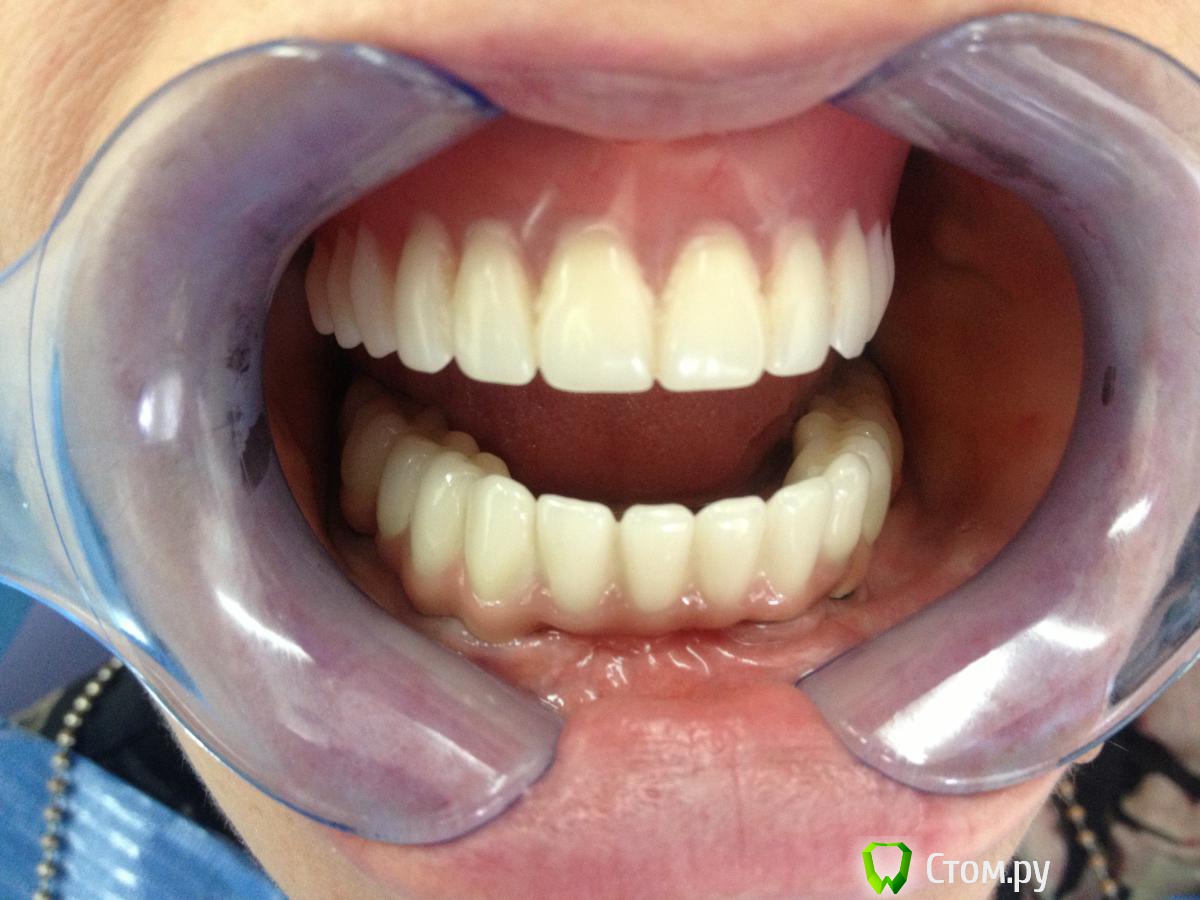

MaxDok Опубликовано 15 февраля, 2014 Поделиться Опубликовано 15 февраля, 2014 (изменено) Интресует правильный ли дизайн промывного пространства ?Критикуйте коллеги. Изменено 15 февраля, 2014 пользователем MaxDok 10 Ссылка на комментарий

MaxDok Опубликовано 15 февраля, 2014 Автор Поделиться Опубликовано 15 февраля, 2014 Красиво! Это цементная фиксация? Каркас литой, а сверху керамика или пластмасса? Спасибо! Цементная,ретракцию везде делал,суперфлоссы во все промежутки в момент цементировки.Каркас изготовлен по технологии лазерного спекания ,облицован керамикой . Ссылка на комментарий

MaxDok Опубликовано 17 февраля, 2014 Автор Поделиться Опубликовано 17 февраля, 2014 //////почему решили консольными концами закончить зубной ряд, и что за керамика?, выглядит неплохо)))/////Тут практически везде было расщепление , в области семерок не проходило . А так как передне задний размер конструкции позволяет спать спокойно , то не задумываясь выбрали такой вариант . Керамика Noritake . Спасибо моему зубному технику , старался . Он кстати на форуме тоже иногда появляется . Ссылка на комментарий